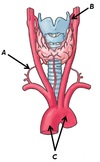

Name the three origins sites (A, B and C) and the one insertion site (D) of the deltoid muscle

A - Spine of scapula

B - Acromium process of scapula

C - Lateral 1/3rd of clavicle

D - Deltoid tuberosity of humerus